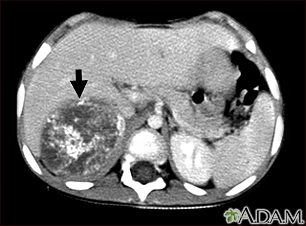

Neuroblastoma in the liver - CT scan